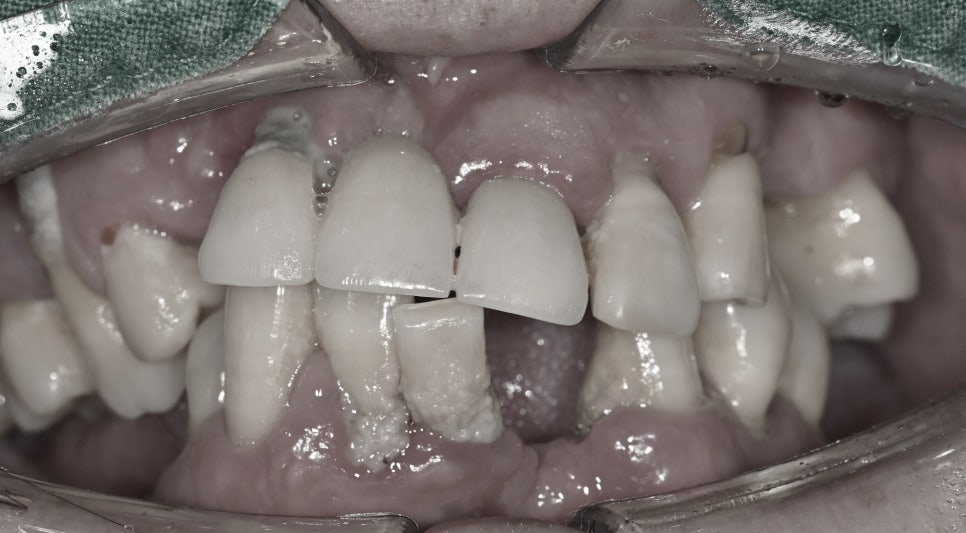

뿌리까지 퍼진 염증은

치조골 즉 뼈에도 영향을 주었습니다.

점차 골이 흡수되었고

그 양이 늘어나면서

여러 개의 치아가

흔들리는 결과를

가지고 왔습니다.

잇몸에서는 피가 나고

눌렀을 때 농까지 나오고

있었습니다.

염증이 파급된 정도가 심하며

이로 인하여 잔존 치조골의 양이

매우 부족한 상태였습니다.

이를 꽉 잡아주고 지지하기 위해선

뼈의 양이 중요한데요,

지금 현재는 거의 다 소실되어

동요가 심각했습니다.